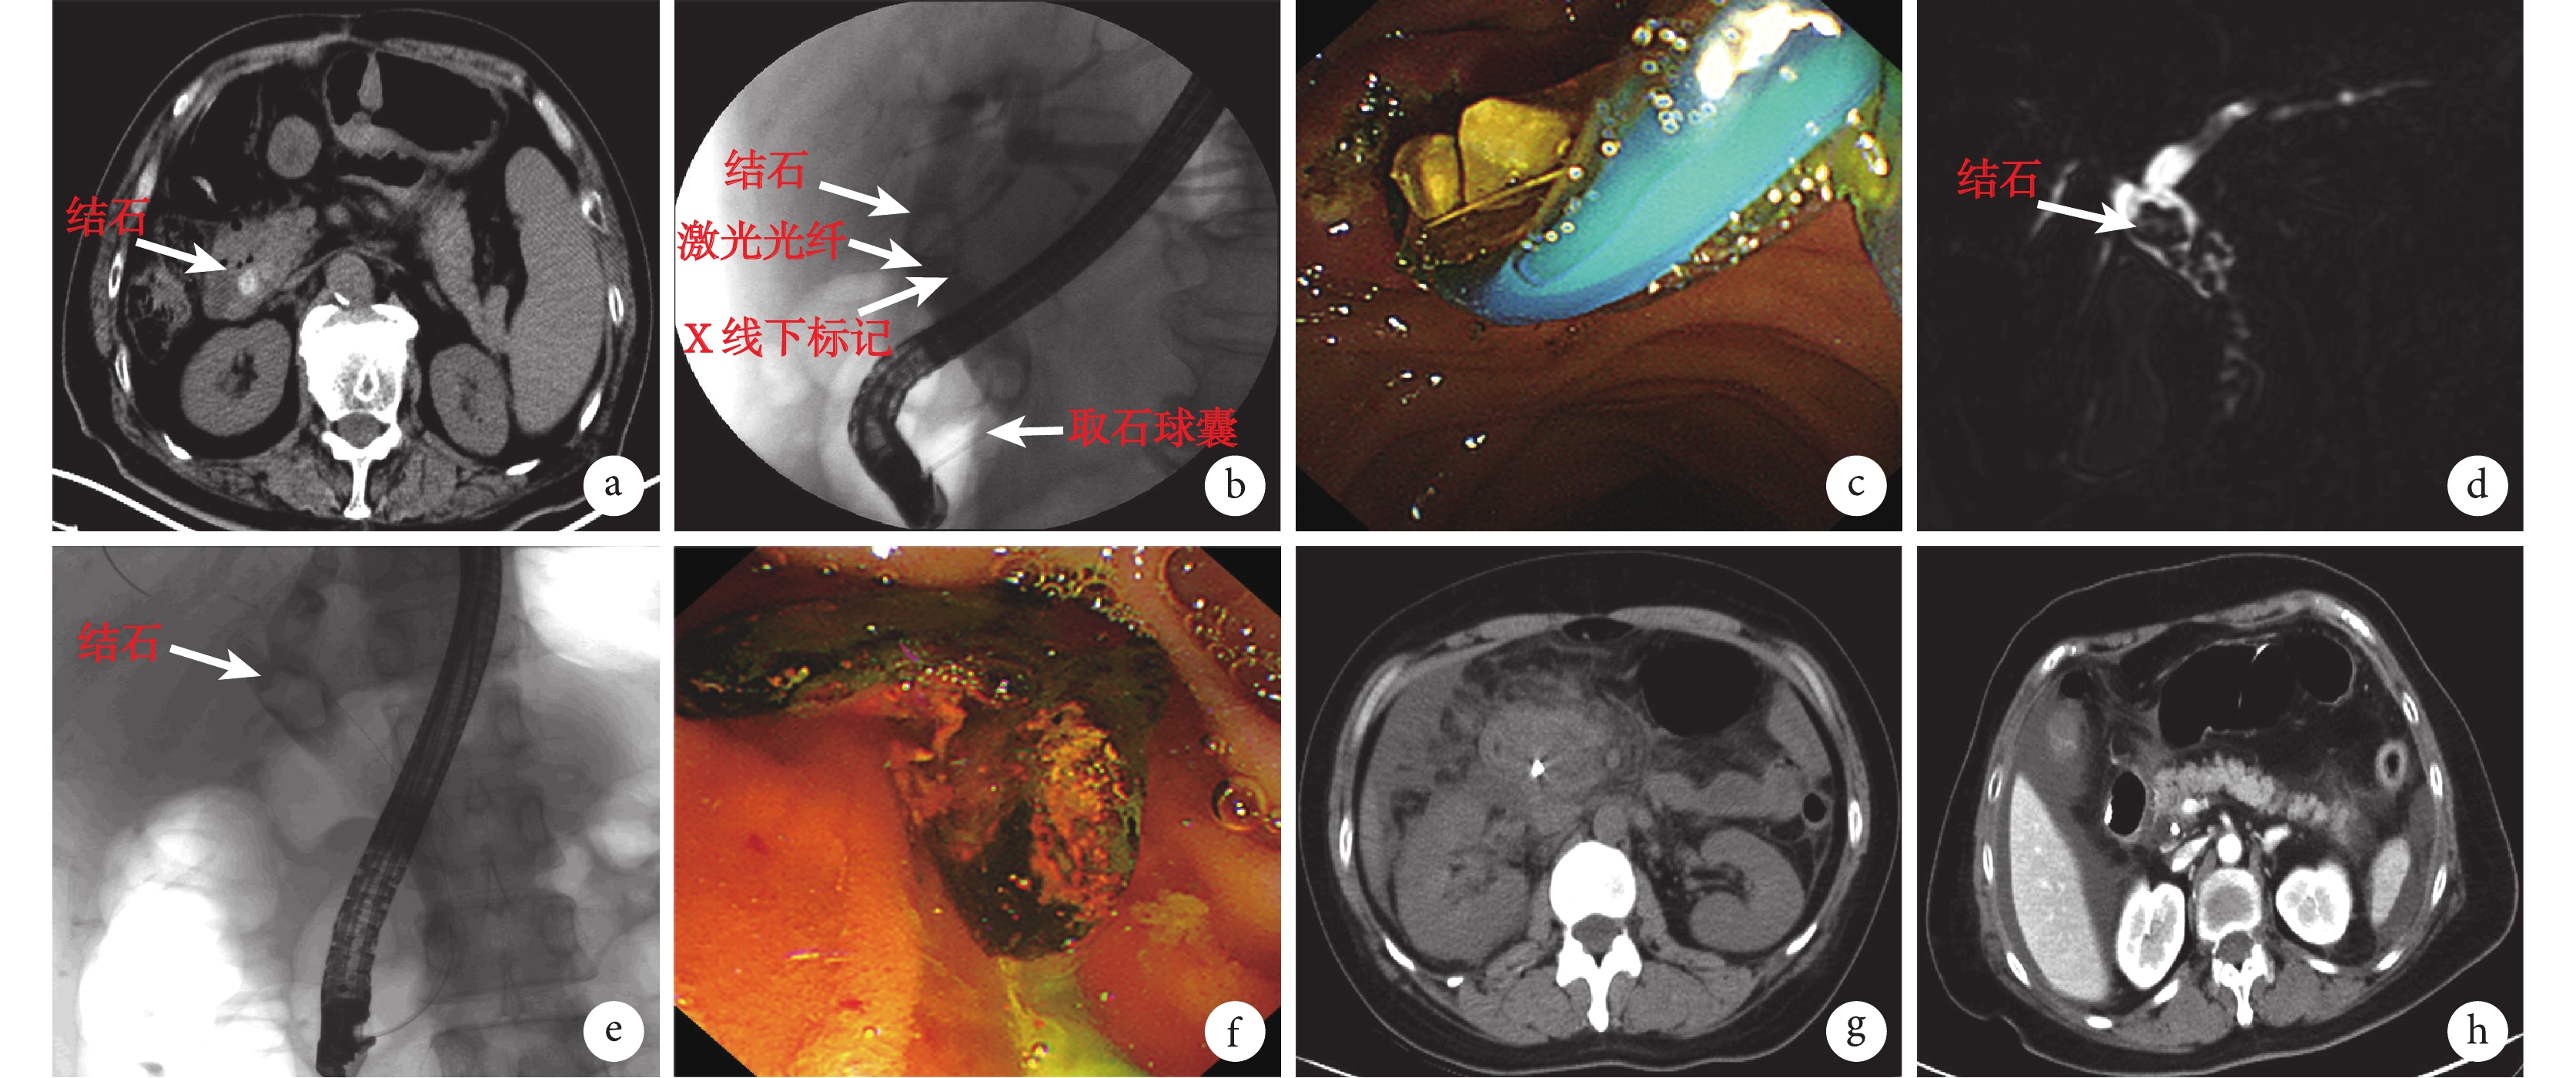

① 主要設備有 Olympus JF-260 十二指腸鏡、愛爾博 200D 電刀、U100 plus 雙頻雙脈沖激光膽道碎石機、BML-3 機械碎石網籃、取石網籃、氣囊導管、超滑導絲、鼻膽管、各種塑料支架等。② ERCP 手術過程:術前禁食 12 h,均在利多卡因咽喉部麻醉下行 ERCP+內鏡下乳頭括約肌切開術(endoscopic sphincterotomy,EST),先插管、造影、切開后再行球囊擴張。術前常規注射鹽酸哌替啶和阿托品(有禁忌證者不用),術前不常規給予抗生素。治療過程中必要時吸氧,同時行氧飽和和心電監護。結石取出后均放置鼻膽管引流,再行膽總管造影,以確認結石徹底清除。若結石一次難以取凈或取石失敗者置入膽管塑料支架,3 個月后再次行 ERCP 取石或行手術治療。術后暫禁食,給予二代頭孢預防感染,術后第 1 天查血尿淀粉酶,若正常則第 2 天進食,若異常則監測至正常后進食。③ 對于術前影像檢查(圖 1a)明確且膽總管結石較大(結石超過膽總管直徑或直徑超過2 cm)者術中采用激光碎石后取出,其具體操作為:插管成功后造影(圖 1b)以明確結石位置,在光纖頭部放置可在 X 射線下顯影的標記(取自斑馬導絲頭部),光纖從取石球囊導絲通道并通過十二指腸鏡進入膽總管,打開球囊與膽總管直徑一致,頂住結石防止結石移位,并在 X 射線透視下明確光纖頂住結石后碎石(圖 1c);對于術前影像學檢查(圖 1d)或術中造影(圖 1e)顯示膽總管內結石可能無法用網籃一次性取出者則術中用機械碎石網籃套住結石后,用加壓手柄碎石后取出至十二指腸腔內(圖 1f)。兩種方法碎石后,使用取石網籃和取石球囊取出膽總管內結石。

a–c:激光組術前腹部 CT 檢查(a)、ERCP 術中影像(b)、ERCP 鏡下影像(c);d–f:機械組術前腹部 CT 檢查(d)、ERCP 術中影像(e)、ERCP 鏡下影像(f);g、h:激光碎石(g)后胰腺炎 CT 影像結果和機械碎石(h)后肝內膽管穿孔的 CT 影像結果

2.3 2 組患者的死亡及并發癥情況

2 組均無圍術期死亡患者。2 組患者的術后并發癥情況見表 4。從表 4 可見,激光組的總并發癥率和結石殘留率均明顯低于機械組(P<0.05),而 2 組間術后出血、術后胰腺炎、穿孔和膽管感染率比較差異無統計學意義(P>0.05)。激光組術后胰腺炎患者復查 CT 影像結果顯示可見胰頭及十二指腸周圍滲出明顯(圖 1g),所有并發癥均通過保守治療后痊愈;機械組碎石后復查 CT 可見腹腔內大量積液,術中證實為膽汁樣液體,并在肝左外葉找到膽管穿孔(圖 1h),1 例肝左外葉穿孔和 1 例膽總管穿孔患者均通過手術治療后好轉,有 1 例術后出血患者通過輸血、止血治療后好轉,有 2 例壞死性胰腺炎患者通過外科手術治療后好轉,13 例結石殘留患者均置入膽總管塑料支架后通過二次或多次手術后取出膽總管結石,其余患者的并發癥均通過保守治療后好轉。